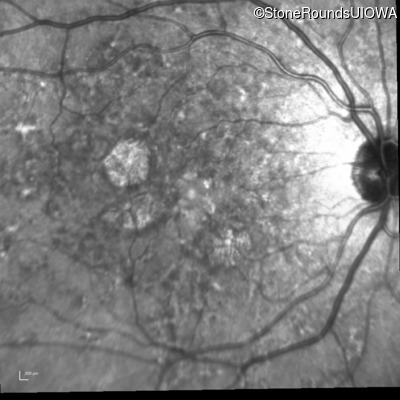

Infrared Fundus Photograph - Right - 20/25 -2

Exemplar

Infrared Fundus Photograph - Left - 20/25 -1